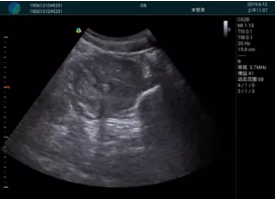

M20查看:囊內(nèi)回聲均勻,邊界清晰,囊壁光滑

M20引導(dǎo)抽吸術(shù)后囊腫消失,原區(qū)域空腔形成,脂肪層與腺體層架構(gòu)發(fā)生改變

便攜超聲引導(dǎo)下人流術(shù)

清晰顯示孕囊,通過軟件包計(jì)算孕齡7w+6d

M20實(shí)時(shí)引導(dǎo),術(shù)中清晰顯示孕囊被破壞和抽吸針的過程,清晰顯示吸引針

抽吸結(jié)束后縱切子宮,孕囊已被完全抽吸,未見明顯殘留

橫切子宮,發(fā)現(xiàn)右側(cè)宮腔靠近宮角處有少許脫模樣殘留

M20引導(dǎo)下,抽吸針找到右側(cè)宮角處再次清掃

二次抽吸后再次進(jìn)行超聲檢查,宮腔未見殘留,宮腔線清晰顯示

超聲引導(dǎo)下可視化人流是技術(shù)安全性的保障,一般對(duì)人流術(shù)設(shè)備預(yù)算不高,M20具備婦產(chǎn)科軟件包,且穿透力圖像質(zhì)量好,既滿足人流引導(dǎo)需要,也可用于床旁超聲的需求。